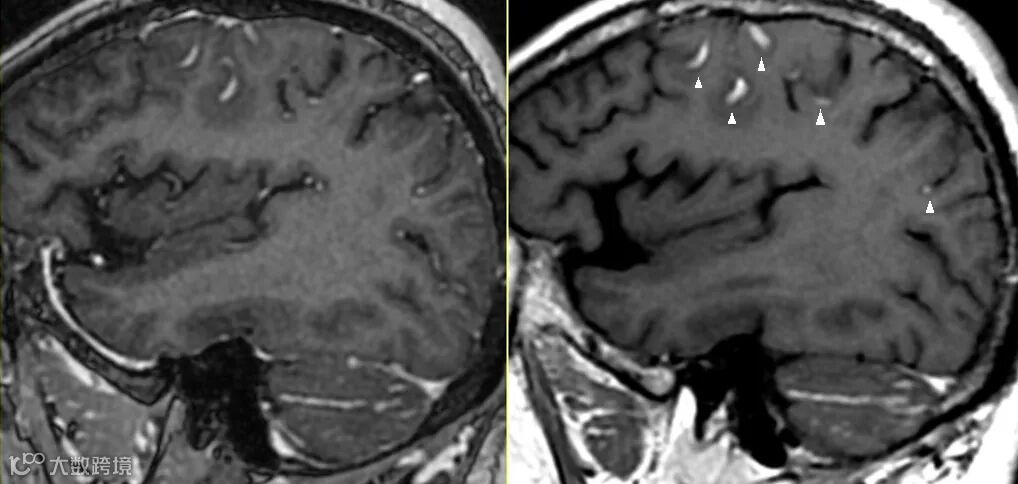

研究表明3D T1可变翻转角自旋回波序列较3D T1磁化准备梯度回波序列对病灶的检出率更高,对颅内强化病灶更敏感,如上图△,两者的扫描体素均为(1.0*1.0*1.0)mm。 -

特别是针对一些小结节病变如脑转移瘤更推荐使用3D T1可变翻转角自旋序列扫描。